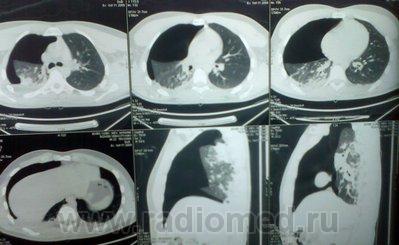

Имеется постравматический пневмоторакс справа (множественные переломы ребер).

1. Какова выраженость пневмоторакса?

2.какое количество жидкости в правой плевральной полости (в мл)?

3. есть ли смещение средостения влево (если есть - то насколько выражено)?

4.есть ли признаки ушиба правого легкого?

1. Advanced right sided pneumothorax

2. mild to moderate right hematothorax  (A зачем определять количество в мл? смысл? Главный вопрос при определении жидксоти в плевральной полости это ответить на вопрос: стоит ли это пунктировать, или нет.).

3. Left mild grade mediastinal shift

4. Right pulmonary contusions

Исходя из этого гемоторакс - средний (крови все-таки больше, чем в плевральном синусе. в вертикальном положении больного), пневмоторакс - тотальный или субтотальный

1. Легкое по объему спалось на 2/3 - 3/4.

2. Около 200 мл.

3. Есть, средней степени.

4. Учитывая отсутствие (или не слишком "большие") переломов ребер вся картина может быть вызвана, главным образом, ушибом легкого.

1. Пневмоторакс субтотальный;

2. Жидкости - около 200,0-250,0 мл (для судебных медиков это важно);

3.Смещение средостения влево умеренное(для судебных медиков это важно);

4. Имеется ушиб правого легкого.

А пневмоторакс-то, клапанный (смещение средостения в противоположную сторону). А никто, и я в том числе, это не отразил. Интересно, почему? Про себя - прозевал.

Такой вопрос перед экспертами не ставился, было отмечено смещение средостения, что свидетельствует о напряженном (клапанном) пневмотораксе.